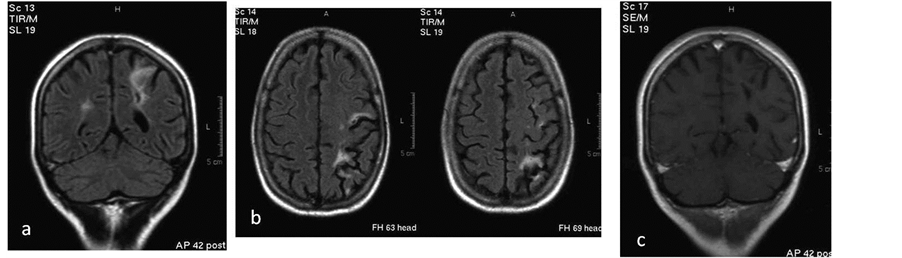

The second patient with seizures revealed small focal lesions less than 1 mm bilateral in the periventricular and subcortical white matter with intense enhancement on the left parietal and right frontal lobe (Figure 2).

Figure 2. (a) Coronal, (b) axial FLAIR sequences show small lesions adjacent to the left occipital horn.